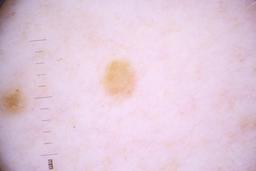

ISIC_4077341

- Challenge 2020: Training

Clinical

| Field | Value |

|---|---|

| acquisition_day | 1 |

| age_approx | 50 |

| anatom_site_1 | Trunk |

| anatom_site_2 | Anterior trunk |

| concomitant_biopsy | False |

| dermoscopic_type | contact non-polarized |

| diagnosis_1 | Benign |

| diagnosis_confirm_type | serial imaging showing no change |

| family_hx_mm | False |

| image_type | dermoscopic |

| lesion_id | IL_9238622 |

| patient_id | IP_1969685 |

| personal_hx_mm | True |

| sex | male |